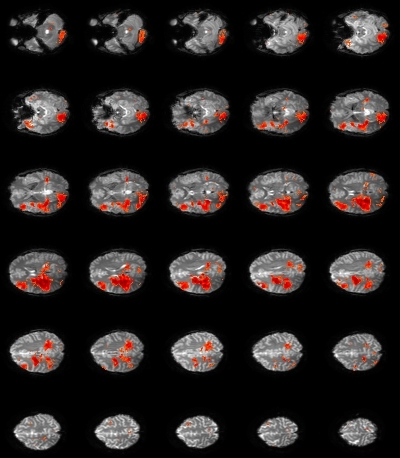

Rationale: Epilepsy diagnosis and treatment benefit from the mapping of interictal epileptiform discharges (IED), which is achieved at much higher spatial resolution with functional MRI than with scalp EEG. In previous studies that use either simultaneous EEG-fMRI (Pittau et al., Neurology 78:1479) or fMRI alone (Khatamian et al., Epilepsy Res 94:177), fMRI signal analysis is based on amplitude increases in each voxel, which represent increased neural activities during IED. However, IED are also accompanied by increased neural synchronization across a local area (e.g. 6-20 cm2) surrounding the IED (Wennberg et al., Clin Neurophys 122:1295). This encouraged us to develop new fMRI analysis paradigms based on the increase in synchronization of fMRI signals across voxels within a local area during IED. Such synchronization can be measure by local degree centrality (LDC), a network metric of local functional connectivity (Sepulcre et al., PLoS Comp Biol 6:e1000808).Methods: One-hour simultaneous scalp EEG (32 channels) and whole-brain fMRI (resolution: 3 mm, 2.5 s) data were acquired from 5 patients with focal epilepsy, and pre-processed using steps similar to that in previous studies. For IED mapping that uses EEG, fMRI data of 20 s duration around each IED event identified from EEG were stitched together into an IED-containing time segment, and IED-absent time segments of the same duration were constructed for comparison. LDC was computed for each time segment and each voxel as the sum of the fMRI signal correlation coefficients between this voxel and all voxels within 1.4 cm distance (i.e. an area of > 6 cm2). The statistical significance (z-score) of LDC difference between IED-containing and IED-absent time segments was mapped. For IED mapping without EEG, LDC was computed for segments of 40 s duration slid across time, effectively creating a time series of LDC values for each voxel. Using cluster analysis (Khatamian et al.), voxel clusters that have the maximum LDC value at the same time were isolated and then inspected visually to identify the cluster most likely associated with IED.Results: For mapping that utilizes EEG, focal regions with significant LDC increases during IED were identified in all 5 patients, and their locations were concordant with EEG. Figure 1 shows the LDC z-score map in a patient with EEG spikes in left temporal lobe. The LDC-based approach performed better than the conventional EEG-fMRI method, which failed to identify concordant activation regions in 2 of the 5 patients who had relatively fewer events. For mapping without EEG, the LDC-based approach identified concordant voxel clusters in 3 patients, again with better performance than the conventional method. The resultant map (Figure 2) is often less specific than when using EEG and involves resting-state networks unrelated to IED, consistent with previous studies.Conclusions: The new method based on local fMRI signal synchronization is at least as effective in mapping interictal activities as the conventional methods based on signal amplitude, both when using simultaneous EEG to identify IED events and when without EEG.